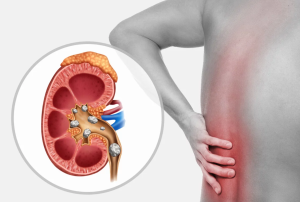

●المغص الكلوي؛ الألم الحاد في أسفل الظهر أو الخصر.

قد تمر حصوات الكلى الصغيرة عبر المسالك البولية من تلقاء نفسها، مما يسبب ألما طفيفا أو لا يسبب أي ألم. قد تتوقف أو تنحشر حصوات الكلى الكبيرة على الطريق، حيث يمكن أن تمنع حصوات الكلى التي تنحشر تدفق البول، مما يسبب ألما شديدا أو نزيفا.